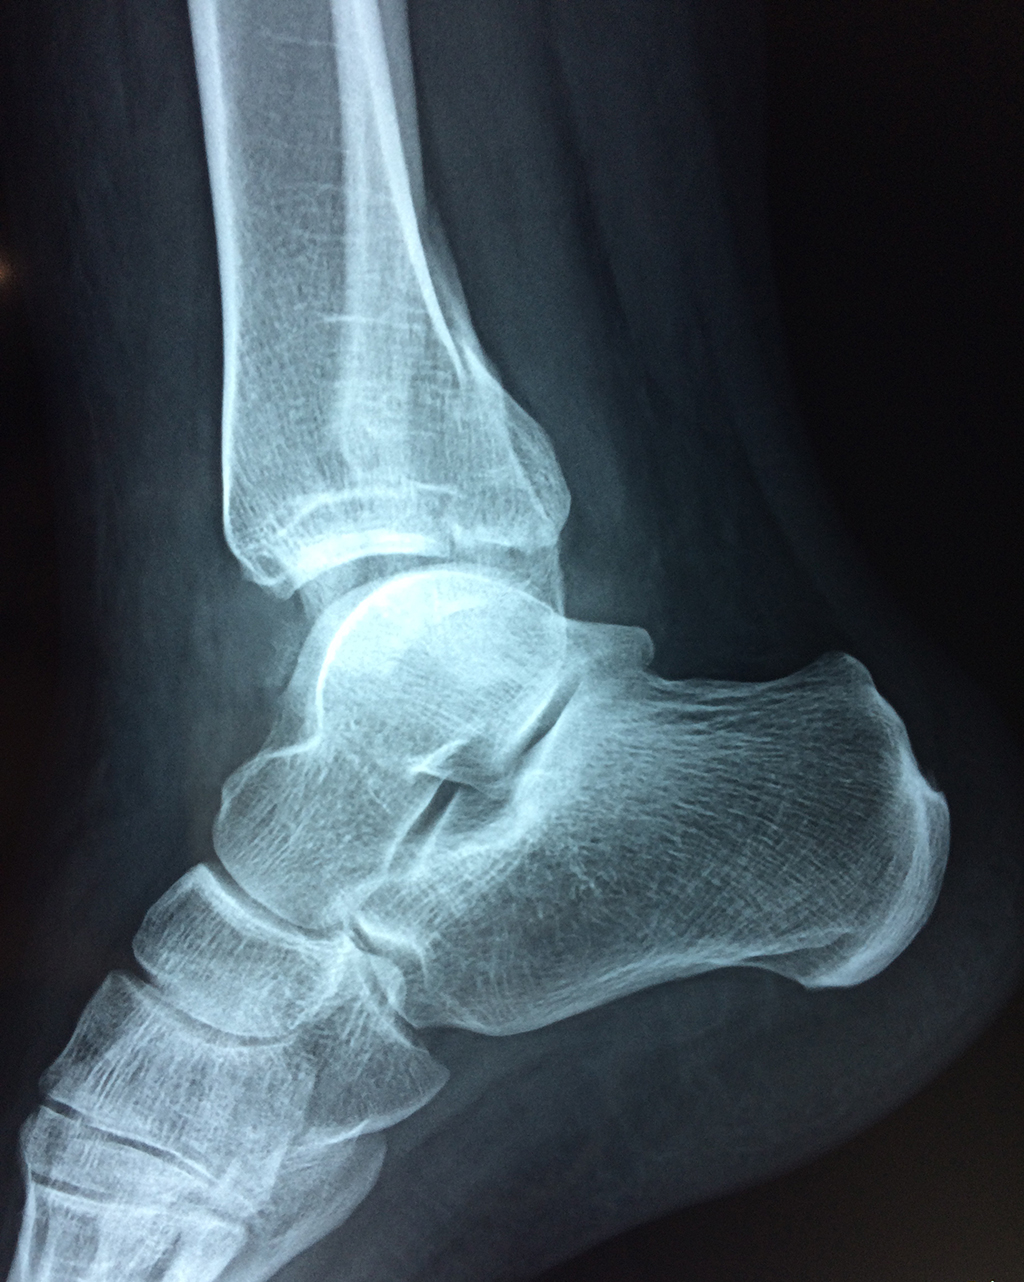

Una fractura de tobillo es la rotura de uno o más de los huesos del tobillo. Estas fracturas pueden ser:

- Los extremos de los huesos están desalineados entre sí (desplazados).

- La fractura se extiende hasta la articulación del tobillo (fractura intra-articular).

Cuando se necesita cirugía, es probable que esta implique el uso de clavijas de metal, tornillos o placas para sostener los huesos en su lugar mientras la fractura se consolida. Los elementos de soporte pueden ser temporales o permanentes.